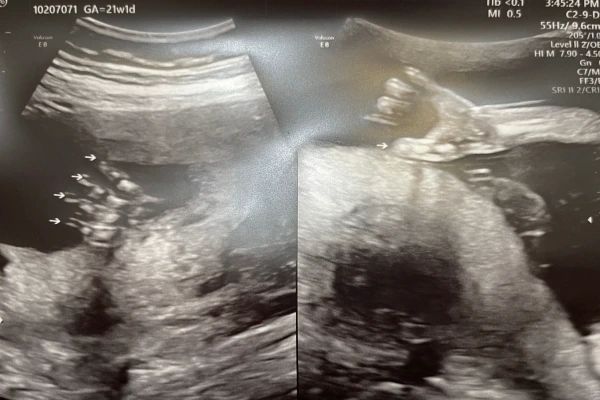

작디작은 새싹이에서 이제는 눈코입도 다 보이고, 꼬물꼬물 거리던 팔다리도 모양을 갖춰가네.

평소에 그렇게 엄마 배를 뻥뻥 차대던 건강이 다리가 저런 모습이었구나.

꼬물꼬물 작은 손 얼른 잡아보고 싶다~!!